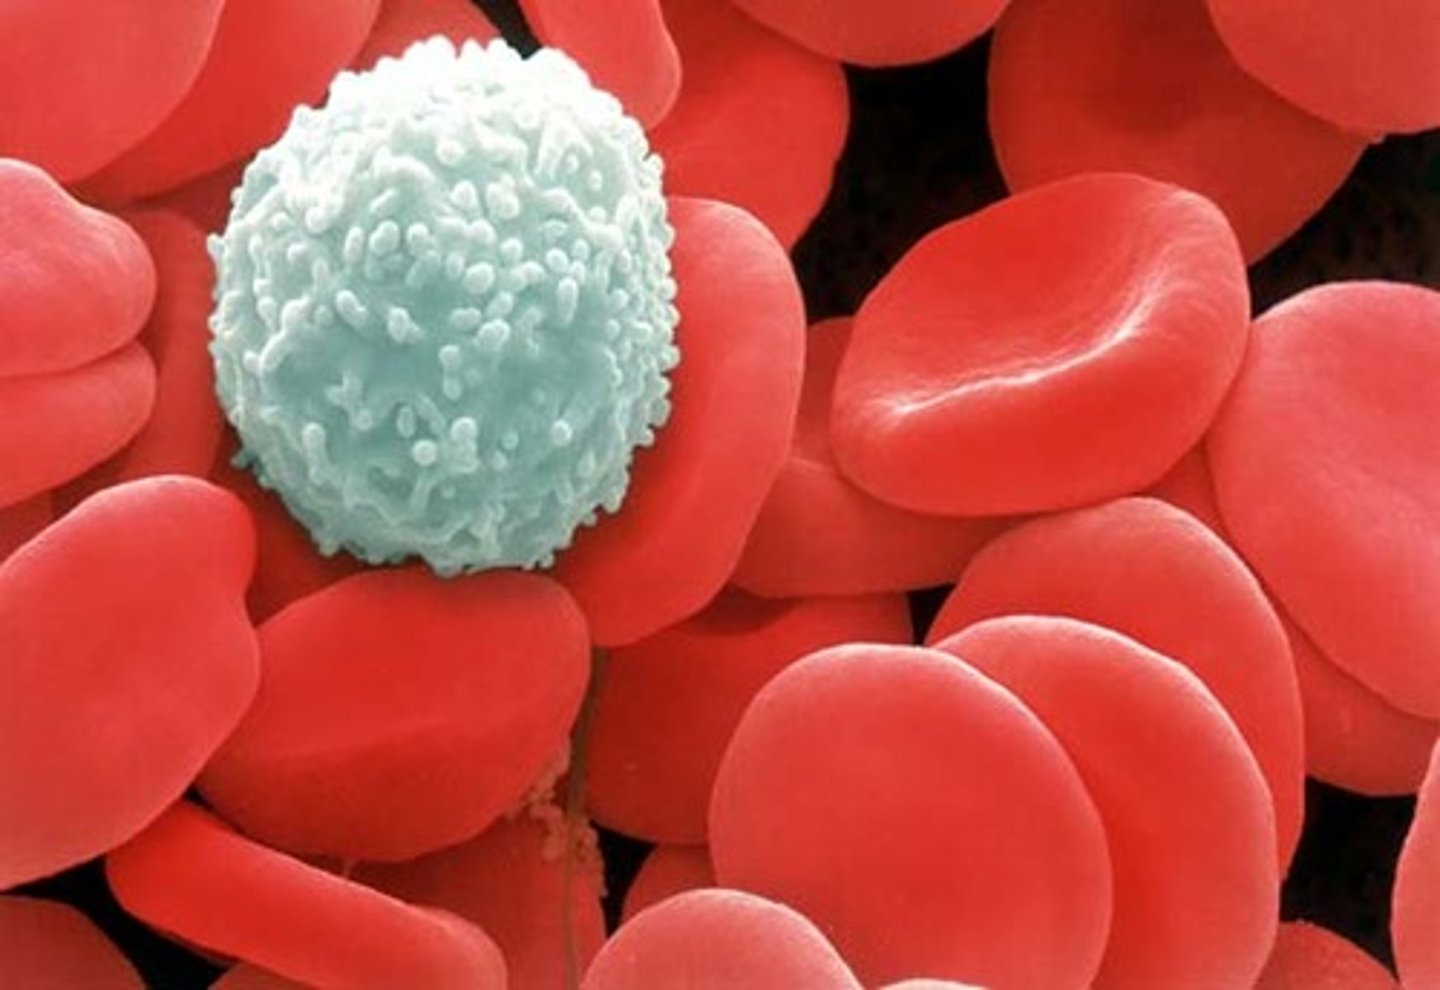

Leukocytes

White blood cells